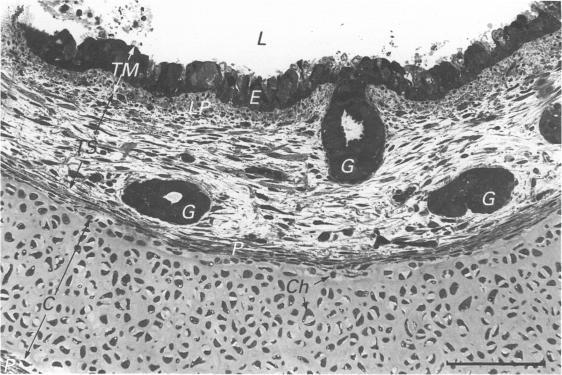

Twenty two mid-trimester human fetal tracheae were processed for light microscopy and scanning, transmission and freeze-fracture replication electron microscopy. The tracheal pseudostratified columnar epithelium was found to be composed of four cell types: ciliated in various stages of development, non-ciliated, basal and degenerating cells. The ratio of ciliated to non-ciliated cells was approximately one-to-one. The non-ciliated cells were of two morphological sub-types. Of these, the vast majority contained characteristic secretory granules, approximately 0.5 microns diameter, found in abundance within the apical region of the cell cytoplasm. The second sub-type of the non-ciliated cell, the well differentiated goblet cell, was observed very infrequently. The relatively large number of non-ciliated cells in the fetal tracheal epithelium suggests a transition stage to the adult where the ratio of ciliated to non-ciliated cells is near 5-to-1. The nature of the first type of the non-ciliated cells, which have not been studied in depth previously, remains obscure. Their probable secretory function is discussed and comparisons are made with previously reported cell types showing similar features, in fetal or adult material from the distal airways of animal and human tissues. Approximately 15 to 20% of the epithelial cells show signs of degeneration. The probable causes of this degenerative process are discussed. Other cell types such as brush cells, endocrine and wandering lymphocytes were not observed. Well-differentiated muco-serous glands were observed within the tela submucosa.

对22个孕中期人胎儿气管进行了处理,用于光学显微镜检查以及扫描电子显微镜、透射电子显微镜和冷冻断裂复型电子显微镜检查。发现气管假复层柱状上皮由四种细胞类型组成:处于不同发育阶段的纤毛细胞、非纤毛细胞、基底细胞和退化细胞。纤毛细胞与非纤毛细胞的比例约为1:1。非纤毛细胞有两种形态亚型。其中,绝大多数含有特征性分泌颗粒,直径约0.5微米,大量存在于细胞质顶端区域。非纤毛细胞的第二种亚型,即分化良好的杯状细胞,很少观察到。胎儿气管上皮中相对大量的非纤毛细胞表明其处于向成人阶段的过渡阶段,成人纤毛细胞与非纤毛细胞的比例接近5:1。此前未深入研究的第一种非纤毛细胞的性质仍不清楚。讨论了它们可能的分泌功能,并与动物和人类组织远端气道的胎儿或成人材料中先前报道的具有相似特征的细胞类型进行了比较。约15%至20%的上皮细胞显示出退化迹象。讨论了这种退化过程的可能原因。未观察到其他细胞类型,如刷状细胞、内分泌细胞和游走淋巴细胞。在黏膜下层观察到分化良好的黏液浆液腺。